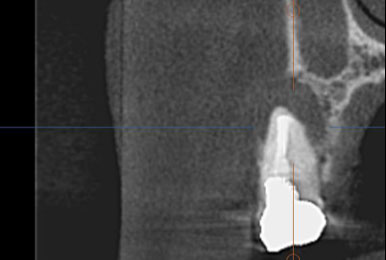

- 「CT」の活用立体的に患部を確認

保険治療では発見することが難しい4つ目の神経を

歯を大きく削らずに見つけられます。